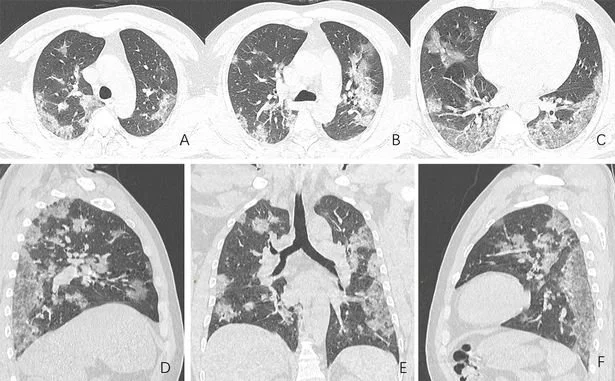

Ha incluso filmati ad ultrasuoni dei suoi polmoni, che hanno dimostrato di essere gravemente colpiti dalla malattia.

Il dottor Chen ha detto alla LBC che il coinvolgimento dei polmoni era la parte più "preoccupante della malattia", quindi è stato sollevato nel vedere che erano "completamente normali".